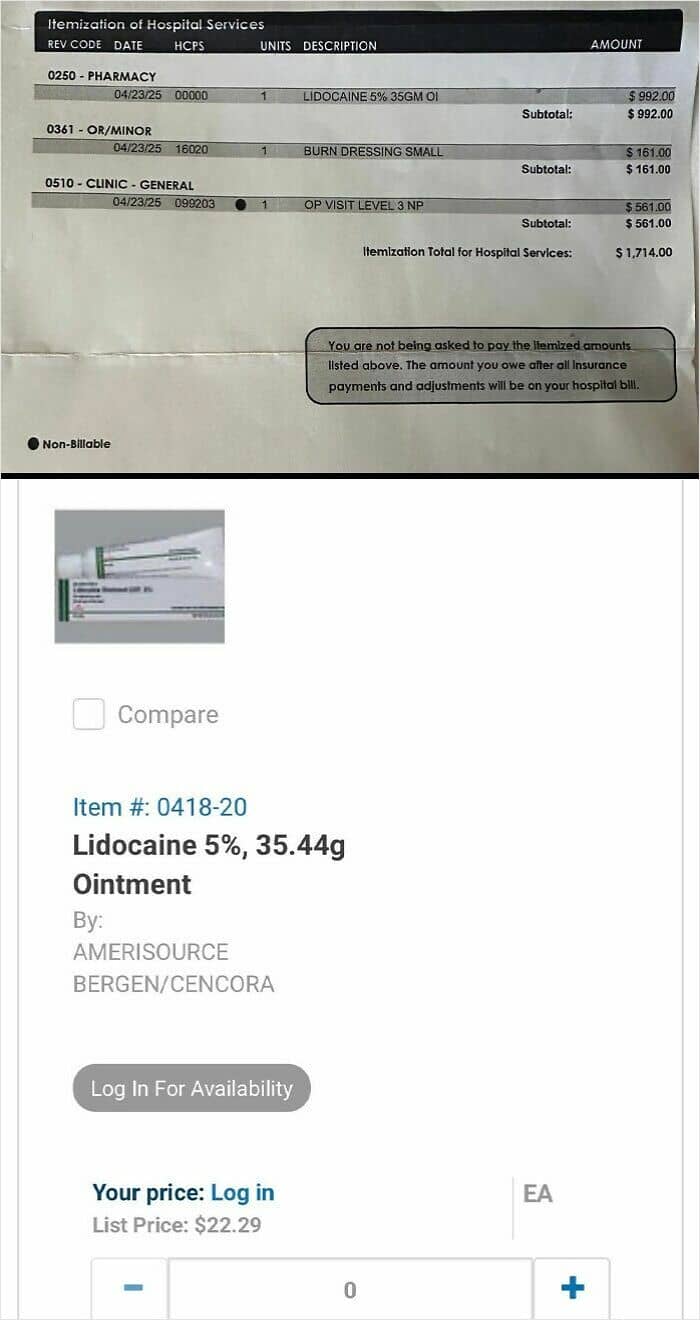

#84 Charged $992 For A $22 Tube Of Lidocaine At Chippenham Hospital In Richmond, VA

I was in a car accident a few months ago and visited the burn center for a minor airbag burn. I spent 20 minutes with a doctor whose time was worth $561, but apparently their magic Lidocaine was worth the $992 at a 5000% mark up. Whenever you call the hospital to get information about or dispute the charge, they always route you to a collections agency. The collections agency just claims they don’t dispute the charges and offer to take $100 off the bill. Their supervisor does the same thing.

I was never provided an estimate. I never agreed to pay this amount. They didn’t even give me the tube of lidocaine. Because I have a thousand dollar deductible, I’m now seriously in the hole for something I would have gladly picked up from the pharmacy. It’s obvious they survive by spinning you in circles until you give up.